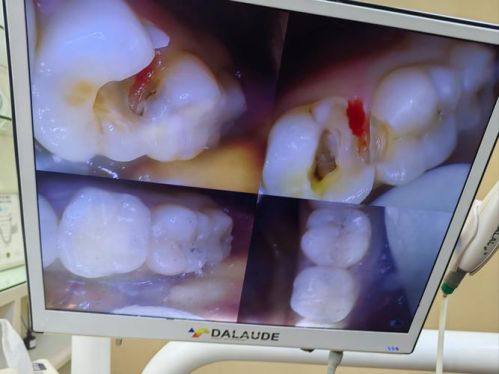

一般情况下,补牙是可以进行医疗保险报销的。牙科纳入医疗保险范围的项目主要有补牙(包含基本材料、治疗费)、拔牙、治疗牙周病、牙龈炎等牙病发生的费用。对于常规的补牙,只要是医疗保险范围内的基本材料和治疗费,就可以走医疗保险报销程序。不过,这里有个重要前提,就是需要在定点医院的口腔科治疗才能享受医疗保险报销。像单纯补牙这种情况,也就是龋齿损伤范围不大,只靠去除龋齿或进行针管治疗(杀神经),然后用材料补上就能修复的,是可以走医疗保险报销的。例如,小李的牙齿有轻微龋齿,在定点医院口腔科进行了补牙,使用的是医疗保险范围内的材料和治疗方法,末尾就顺利进行了医疗保险报销。